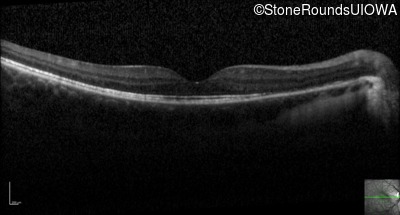

Optical Coherence Tomography - Left - 20/50

Exemplar / OCT Stack